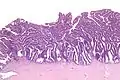

Intermediate magnification

The name of the lesion describes it microscopic appearance. It has nipple-like structures with fibrovascular cores (papillae) that are long in relation to their width (villus-like), which are covered with a glandular pseudostratified columnar epithelium.